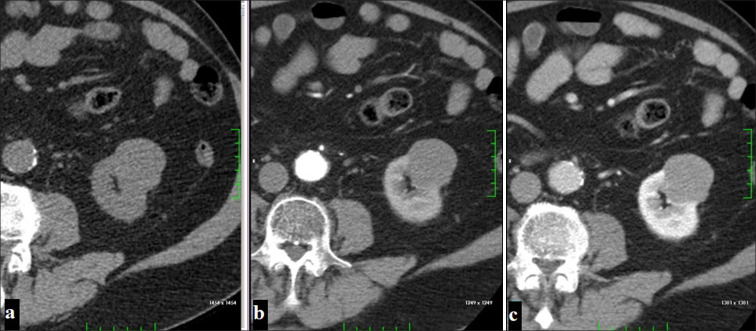

本文综述了计算机断层扫描(CT)和磁共振成像(MRI)对肾细胞癌(RCC)亚型的评价。肾细胞癌是一种具有不同组织病理学亚型的恶性肿瘤,约占成人肾肿瘤的90%。据报道,这些亚型在临床行为、治疗反应和预后方面存在显著差异。本研究比较了透明细胞RCC (ccRCC)、乳头状RCC (pRCC)、疏色RCC (chRCC)、髓质RCC (mRCC)、集管RCC (cdRCC)和多室囊性RCC (mcRCC)等亚型的CT和MRI表现。CT是RCC分期和手术计划的首选成像方法,可以提供肿瘤大小、血管分布和转移扩散的详细信息。另一方面,MRI由于其软组织分辨率和造影剂使用优势,可以更好地表征RCC亚型。该研究关注了每种亚型的不同影像学特征,并详细介绍了这些发现在临床决策过程中的作用。有研究表明,ccRCC在CT上表现为皮质髓质期强烈的对比增强和快速冲洗模式,在MRI上表现为T2A高信号和T1加权成像(T1A)低信号。据报道,pRCC具有低血管特征,对比度增强较低,边界均匀。据报道,chRCC的血管结构较少,在皮质-髓质期表现出适度的对比增强。据报道,mRCC具有侵袭性特征,通常在晚期诊断,而cdRCC具有非常侵袭性的临床病程。据报道,mcRCC在间隔之间含有明显的囊性区域,结构界限分明,通常具有低恶性潜能。因此,详细评估RCC亚型的CT和MRI表现对这些亚型的诊断、治疗和预后起着至关重要的作用。人们强调,本研究的发现将有助于开发更有针对性的肾细胞癌治疗方法。

This review discusses the evaluation of renal cell carcinoma (RCC) subtypes using computed tomography (CT) and magnetic resonance imaging (MRI). RCC is a malignancy with different histopathological subtypes, constituting approximately 90% of adult kidney tumors. It has been reported that these subtypes show significant differences in terms of clinical behavior, treatment response, and prognosis. In the study, CT and MRI findings of subtypes such as clear cell RCC (ccRCC), papillary RCC (pRCC), chromophobe RCC (chRCC), medullary RCC (mRCC), collecting duct RCC (cdRCC), and multiloculated cystic RCC (mcRCC) were compared. It was stated that CT is the first-choice imaging method in the staging and surgical planning of RCC and provides detailed information about the tumor size, vascularity, and metastatic spread. On the other hand, it has been emphasized that MRI allows better characterization of RCC subtypes with its soft-tissue resolution and contrast agent usage advantage. The study draws attention to the different imaging features of each subtype and details the role of these findings in the clinical decision-making process. It has been stated that ccRCC exhibits intense contrast enhancement and rapid washout pattern in the corticomedullary phase on CT and appears hyperintense on T2A and hypointense on T1 weighted imaging (T1A) on MRI. It has been stated that pRCC has hypovascular features, has lower contrast enhancement, and has homogeneous borders. It has been stated that chRCC has a less vascular structure and exhibits moderate contrast enhancement in the corticomedullary phase. It has been reported that mRCC has invasive features and is usually diagnosed at an advanced stage while cdRCC has a very aggressive clinical course. It has been stated that mcRCC contains distinct cystic areas between the septa, has a well-circumscribed structure, and generally has a low malignancy potential. As a result, it has been stated that detailed evaluation of CT and MRI findings of RCC subtypes plays a critical role in the diagnosis, treatment, and prognosis of these subtypes. It has been emphasized that the findings presented in this study will contribute to the development of more targeted treatment approaches in RCC management.